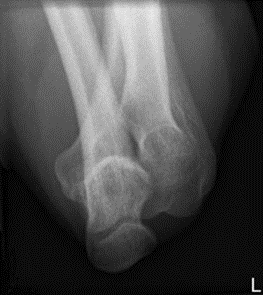

Którą strukturę anatomiczną i w jakiej projekcji uwidoczniono na radiogramie?

A. Wyrostek łokciowy w projekcji osiowej.

B. Staw kolanowy w projekcji tunelowej.

C. Wyrostek dziobiasty w projekcji skośnej.

D. Guz piętowy w projekcji osiowej.